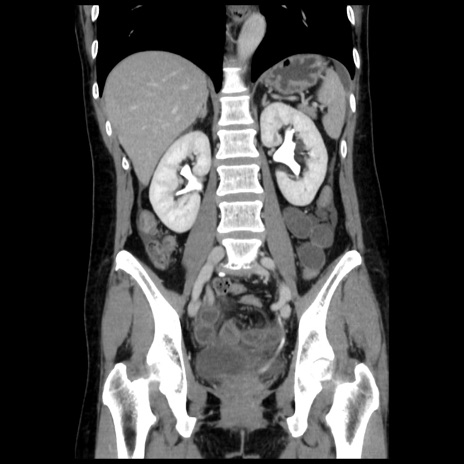

症例10(冠状断像)

【症例】 50歳代女性

【主訴】 腹痛

【現病歴】前日生レバーを食べた。今朝に排便あり。 昼前に突然発症の腹痛を生じ、当院救急外来を受診した。

【既往歴】 子宮筋腫にてで子宮全摘後

【身体所見】 意識清明、腹部:平坦、軟、下腹部やや左を中心に圧痛・反跳痛あり、筋性防御あり

【データ】WBC 7800、CRP 0.07